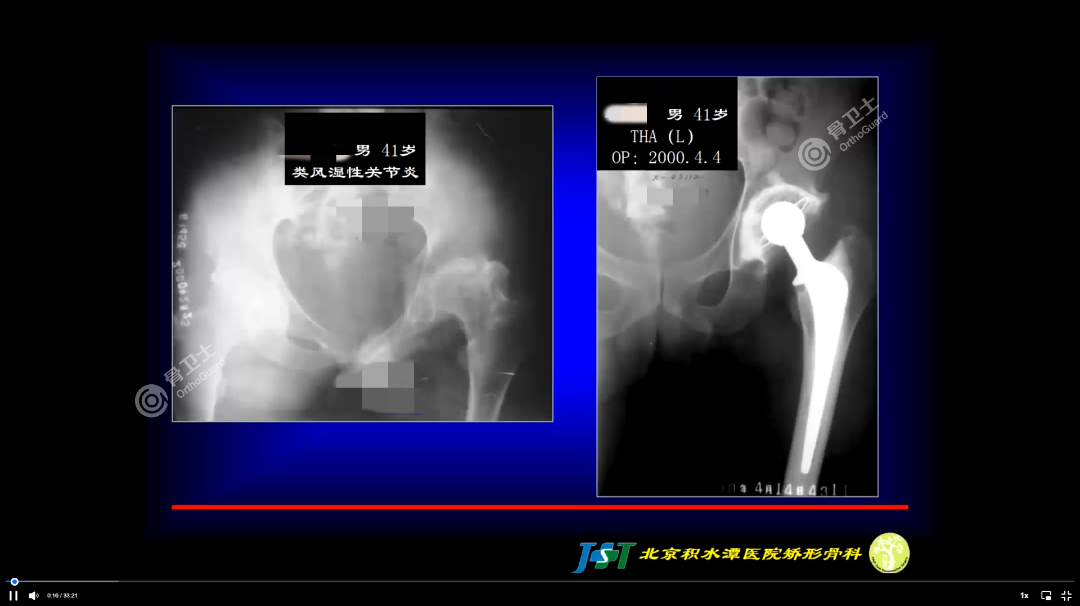

基本情况:患者为男性,41岁,类风湿性关节炎。

周乙雄教授介绍,该患者为类风湿性关节炎,于2000年进行髋、膝关节置换术。由影像资料可以看出,患者骨盆和股骨端骨质不好,骨密度低,考虑到置换后的稳定性,决定使用骨水泥型假体,比较牢靠。